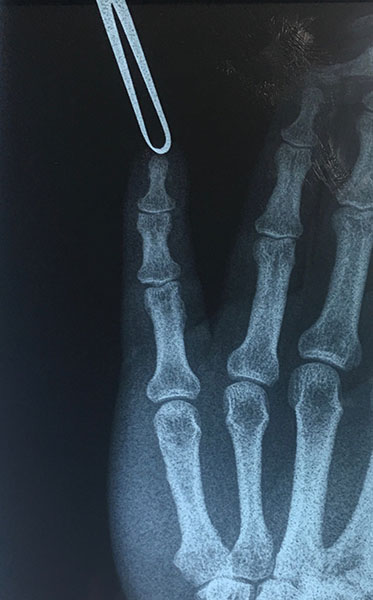

Les muestro el resultado de nuestro paciente 1 mes después de su cirugía en que ya se encuentra realizando fisioterapia y recuperando la función del dedo que casi fue sometido a amputación.